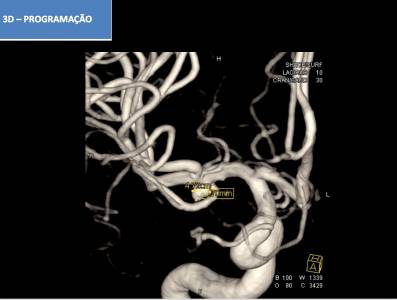

Aneurisma incidental relacionado a artéria cerebral média diagnosticado após investigação de cefaleia. Realizado tentativa de embolização com micromolas sem sucesso, sendo optado pelo tratamendo endovascular com stent redirecionador de fluxo Fred Jr 03 x 14 x 19 mm.